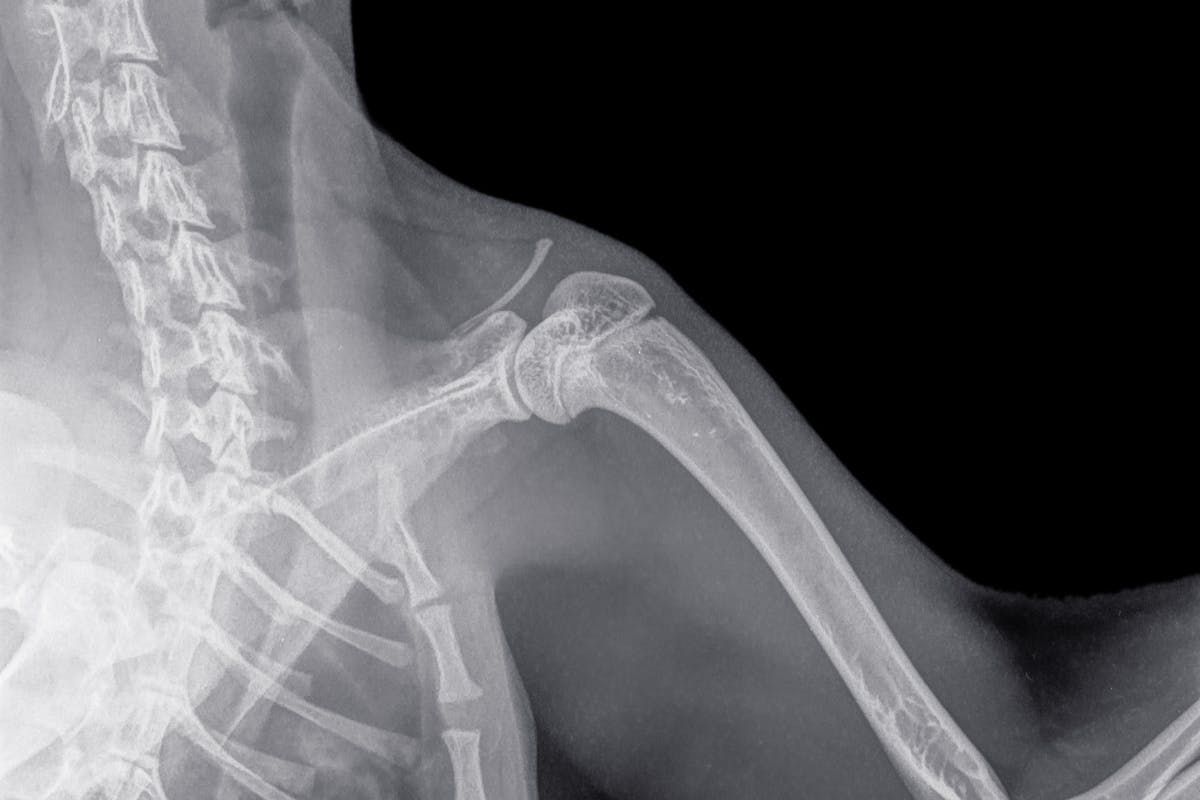

Screening requires a simple physical examination of dogs at least 12 months of age. A licensed veterinarian can take radiographs (x-rays) of both shoulders which will be reviewed by a radiologist at OFA. Dogs can be cleared, or be assessed as having unilateral OCD (one shoulder) or bilateral OCD (both shoulders).

The veterinarian will perform x-rays of your dog’s shoulders. Details about required positioning are outlined on the application form.